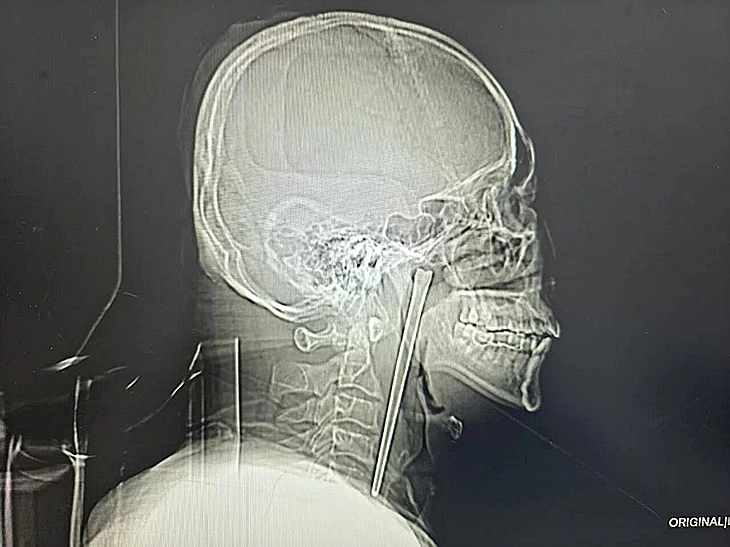

יש מקרים רפואיים שמתחילים בבדיקה שגרתית ונגמרים לכל היותר בהרמת גבה, אבל ישנם גם סיפורים שבהם המשפט הראשון כבר נשמע כמו תקלה בתרגום: גבר סיני הגיע לבית חולים עם כאבים חזקים בגרון, ובצילום שעשה התגלה שם מקל אכילה (צ'ופסטיק) ממתכת באורך 12 סנטימטרים - כזה שהיה תקוע שם, לפי הדיווחים, במשך 8 שנים.

בצילום הרנטגן נחשף המראה הלא ממש שגרתי: מוט מתכתי ארוך, תקוע באזור הלוע. בבית החולים הסבירו כי בתחילה נשקלה פרוצדורה מורכבת יותר, שהייתה כרוכה בחתך בצוואר, אבל וואנג חשש מהסיכונים ובחר לוותר על הניתוח. במשך שנים הוא הסתפק באי-נוחות ובכאבים קלים יחסית, עד שהמצב כבר הפסיק להיות נסבל. בהמשך הצליח צוות רפואי לגבש תוכנית פחות פולשנית, והוציא את מקל האכילה דרך הפה בשלמותו. לאחר כמה ימי השגחה, דווח כי הכאב והגירוי בגרון פחתו משמעותית.